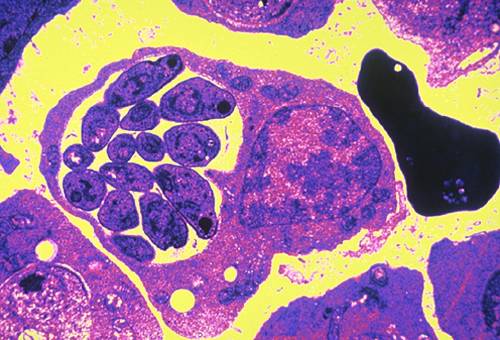

طفيل الملاريا داخل خلية من خلايا الإنسان المصاب